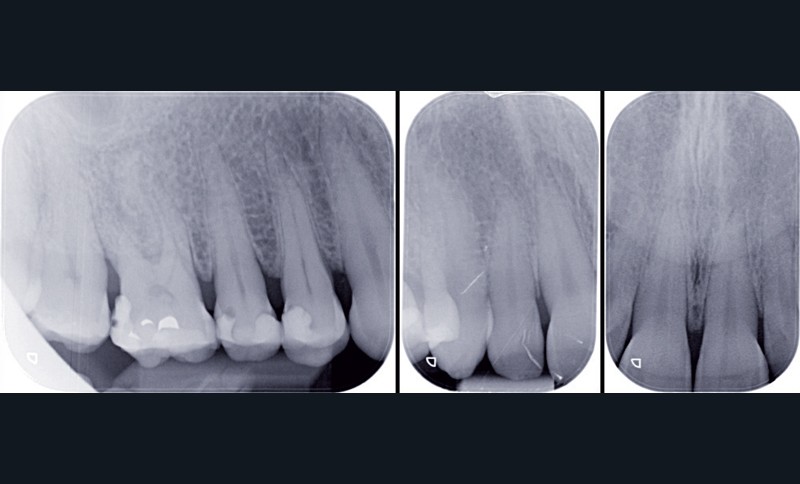

À l’examen radiographique, nous observons, surtout, une alvéolyse modérée généralisée compliquée par des lésions inter-radiculaires de classe I [3] sur 36 et 46 et des lésions carieuses sur les prémolaires maxillaires (fig. 2).